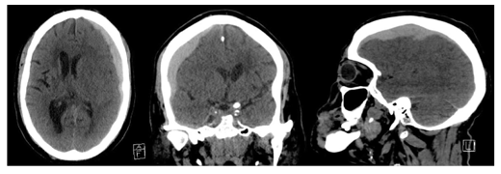

This intracranial hemorrhage appears as a crescent-shaped collection on CT, is often due to tearing of bridging veins, and is more common in elderly and alcoholics.

What is a subdural hematoma?”

In severe TBI, this osmotic agent can be given to acutely lower intracranial pressure by drawing fluid out of brain tissue.”

What is mannitol (or hypertonic saline)?